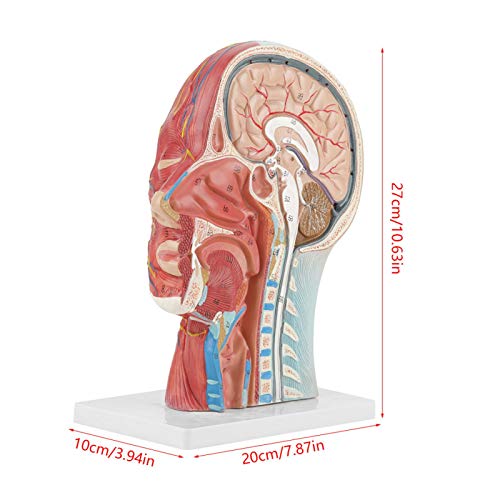

Specificaties:

Materiaal: PVC

Afmetingen: ca. 27 x 20 x 10 cm, 10,63 x 7,87 x 3,94 inch

Gewicht: ca. 886 g